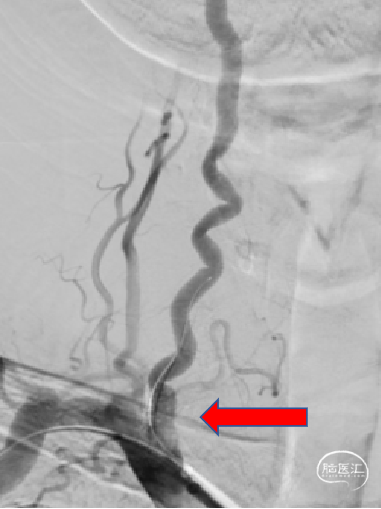

交换6F长鞘定位至右侧锁骨下动脉近右侧椎动脉开口处。使用0.014inch 200cm神途威龙导丝顺利的通过右侧椎动脉V1段狭窄病变,并置于左侧椎动脉V2段,泥鳅导丝置于肱动脉,建立稳定治疗通路。

造影后用锁骨定位狭窄位置,沿神途威龙导丝输送4mm*16mm Bridge椎动脉雷帕霉素靶向洗脱支架通过狭窄段,定位准确后命名压释放支架,造影可见,管腔通畅,前向血流恢复。

术后情况:患者行动较术前灵活,头部昏沉感减轻,言语较前清晰,血压控制良好。于术后第3天出院。